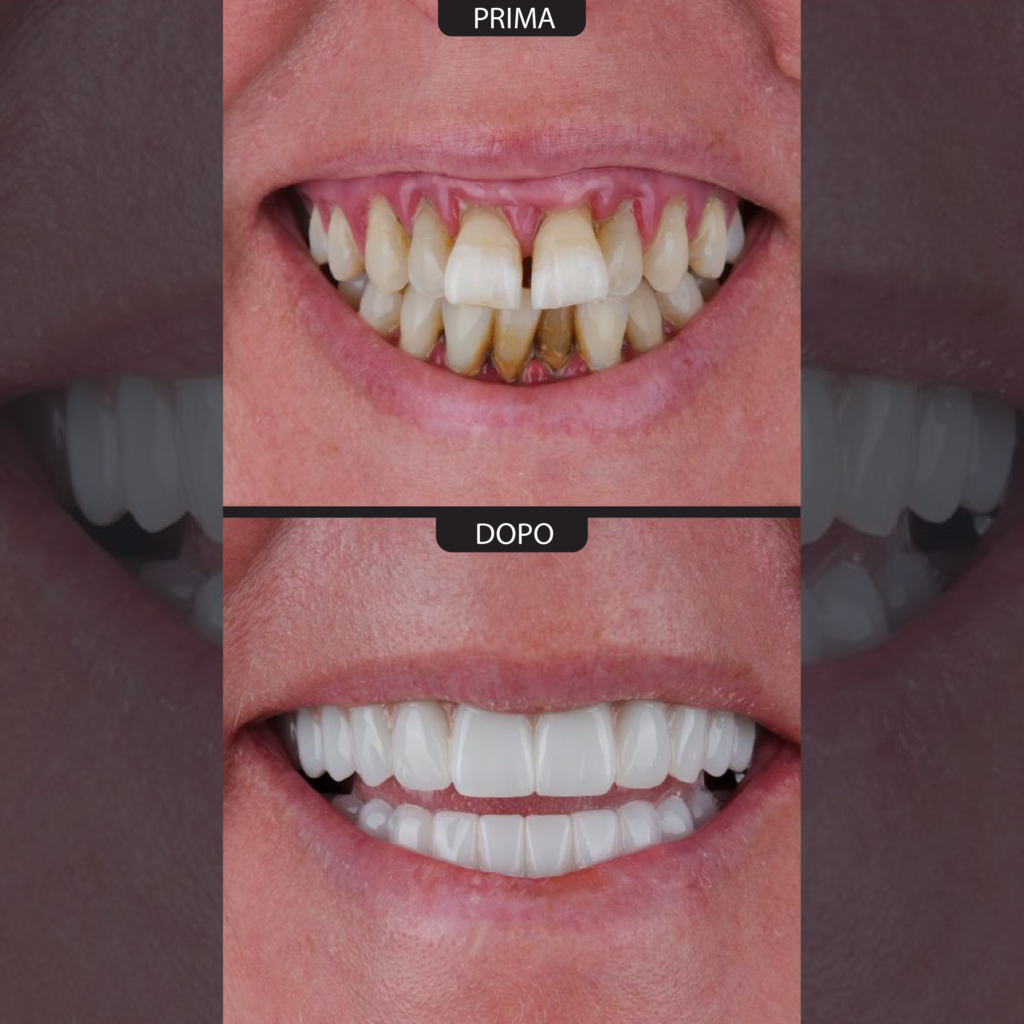

La mancanza di denti, se non trattata, può causare problemi funzionali come difficoltà nella masticazione e riassorbimento dell’osso mascellare. Le tecniche All-on-4 e All-on-6 rappresentano una soluzione efficace sia per la perdita parziale che totale dei denti. Ancorando radici dentali artificiali in modo stabile all’osso e applicando protesi fisse dall’aspetto naturale, è possibile ripristinare estetica e funzionalità. Il numero di impianti necessari viene definito in base alla struttura ossea e al grado di perdita dentale, garantendo un sorriso confortevole stabile e dall’aspetto naturale.